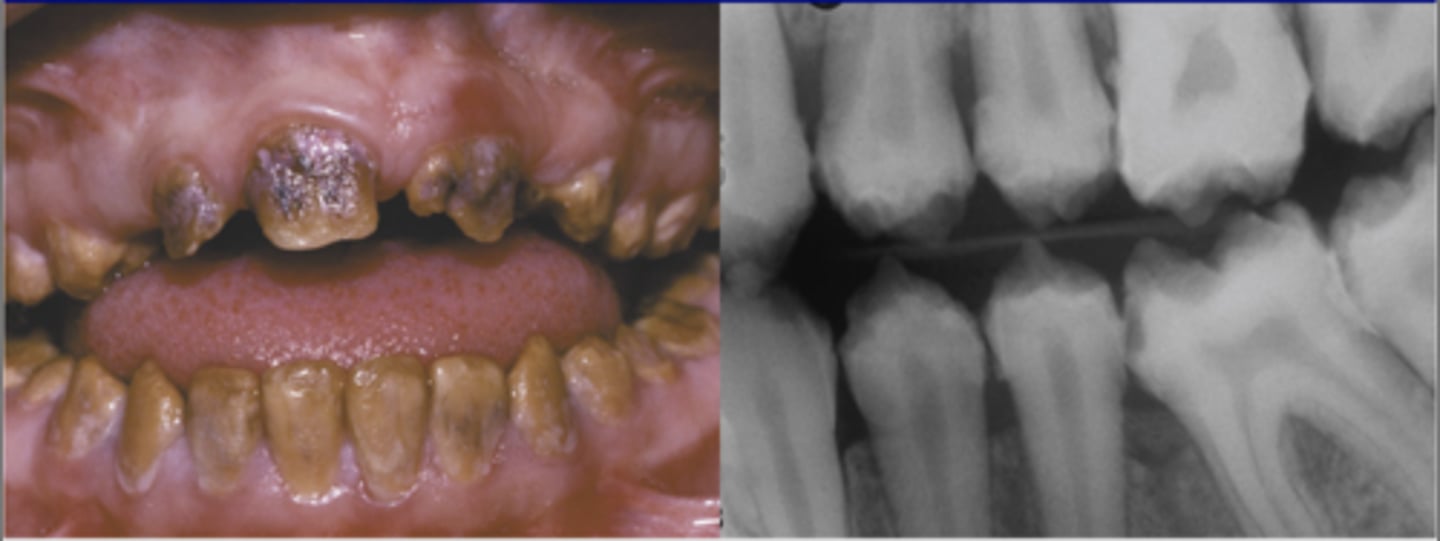

-bulbous crowns

-bluish/translucent color of teeth

-enamel breaks off defective dentin = brown surface

-on XR → no pulp/short roots/periapical radiolucencies